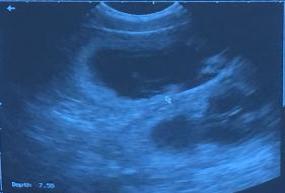

On January 30th I will have an USG done to confirm the pregnancy

January 30, 2016   We have a confirmed pregnancy       puppies due around March 2nd.